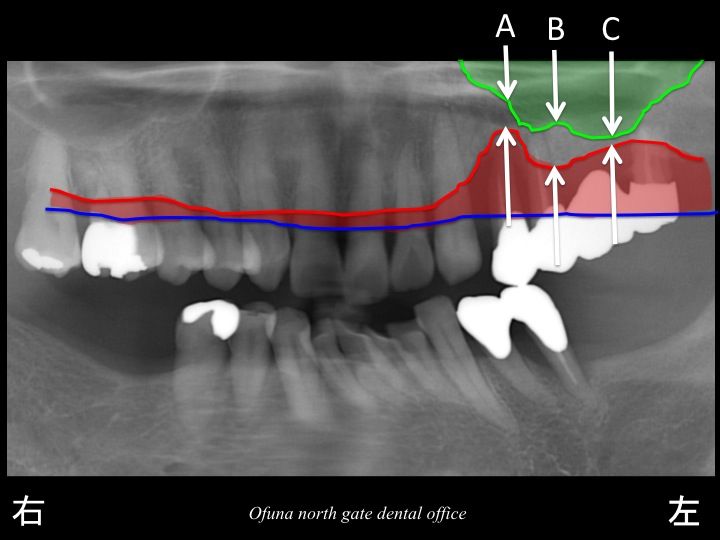

いつものように 骨吸収の状態を分かりやすくするために

骨吸収の状態を線で書いたのが以下のレントゲンになります。

青線が骨吸収を起こす前の骨の位置です。

赤線は、現在の骨の位置です。

かなりの骨吸収が起こっているのが分かるかと思います。

さらに わかりやすくするために、

骨吸収部位を赤色で表示します。

骨吸収が非常に進行しているのが分かるかと思います。

さらに問題があったのが、上顎洞の状態です。

以下の緑線は上顎洞という空洞です。

骨ではなく、穴が開いているのです。

骨の高さを分かりやすく表示したのが以下のレントゲン写真です。

特に A と C の部分では、骨吸収が非常に大きいため、

骨の高さも少ないことが分かるかと思います。